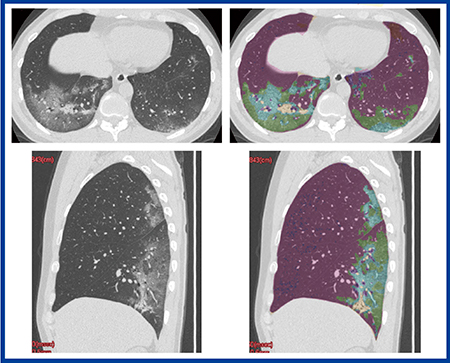

「QZIP-ILD」は,COVID-19肺炎への応用も可能である。症例2は,30歳代,男性,肺の両側にGGOが見られ,典型的なCOVID-19肺炎である。本症例はHRCTで撮影し,1024×1024マトリックス,0.25mmスライス厚で画像再構成を行った。現在,1024マトリックスのHRCTの画像を観察できるワークステーションは限られているが,同社の「Ziostation2」ではこれらの画像データに対応し,MPRでの観察も容易である。病変部を拡大(図3)すると,コンソリデーション内部に,呼吸細気管支と思われる細かい分岐状の気腔(↑)が認められるほか,crazy paving pattern内部では正常肺と比較して小葉が小さいことも確認できる(↓)。「QZIP-ILD」による定量解析結果を見ると,本症例では局所の容積低下はあるものの,肺全体の体積は予測全肺気量の100%で低下は見られず(図4),本症例では肺炎は改善した。

図4 症例2の「QZIP-ILD」による解析結果